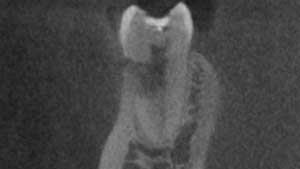

- Figures 9 and 10 show a discontinuation of the uniform outline of the pulpal chamber of tooth No. 19. Furthermore, margins of the lesion are sharp and well defined.

- Diagnosis: internal resorption.